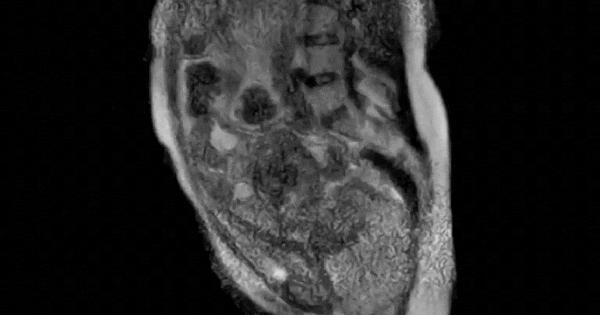

Mới đây, một đoạn video ghi lại cảnh một phụ nữ sinh con ngay trong máy MRI bất ngờ được chia sẻ lại sau hơn 15 năm, nhanh chóng thu hút sự chú ý của cộng đồng mạng.